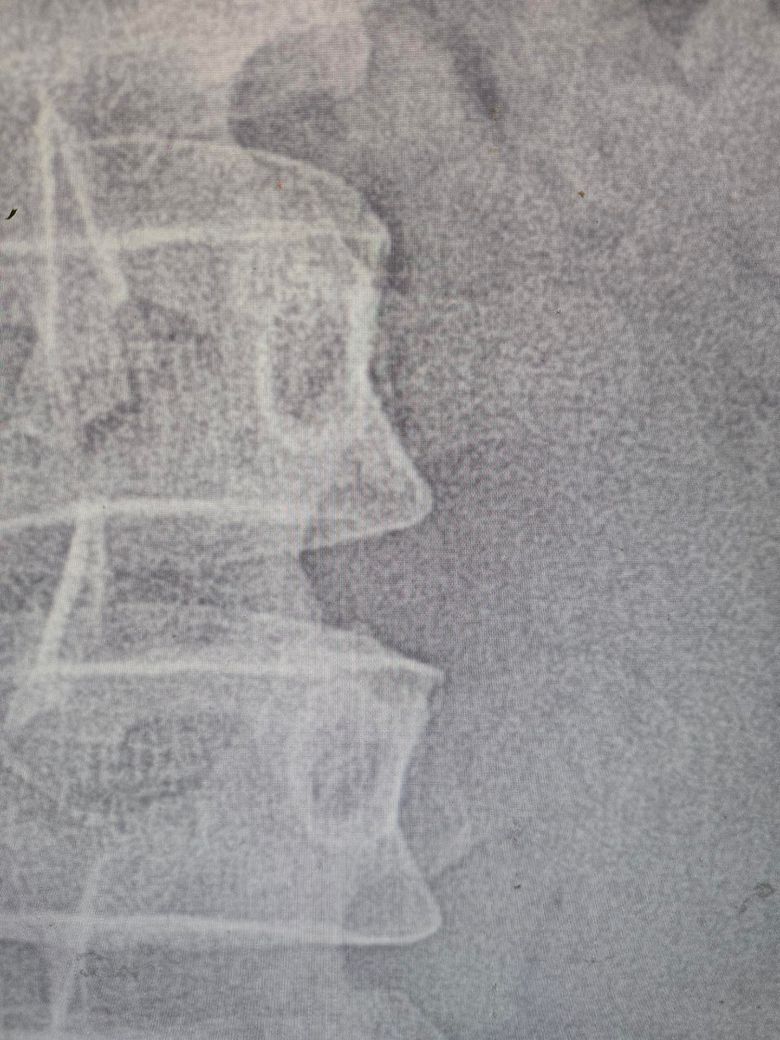

• 3번 째 사진

척추 모서리부분이 날카로와서 그럴수있다는데

3번째?척추 오른쪽 인거같은데 혹시 생긴지 오래된건가요??

척추 뼈가 뾰족하게 튀어나온것은 골극현상으로 이는 척추가 압력을 견디기 위해 스스로 뼈를 덧세우는 퇴행성 변화입니다. 최근의 통증때문이 아니라 현장 일과 사다리 작업 등 허리에 가해진 물리적 스트레스가 수개월에서 수년에 걸쳐 누적되어 생긴 결과입니다. 아침에 통증이 심한 것은 밤사이 경직된 근육이 변형된 뼈 주변조직을 자극하기 때문이며 디스크 이상이 없다면 관리가 가능한 단계입니다. 방치하면 뼈가 더 자라나 주변신경을 누를수 있으므로 코어운동과 스트레칭을 통해 추가 변형을 막고, 자세교정과 작업전후로 근육을 이완해 주는 꾸준히 관리를 병행해야합니다. 답변이 도움됐길 바랍니다!

엑스레이에서 말한 "모서리가 날카로운 것"은 보통 "골극(뼈돌기)"으로, 갑자기 생긴 게 아니라

오래된 퇴행성 변화인 경우가 많습니다.